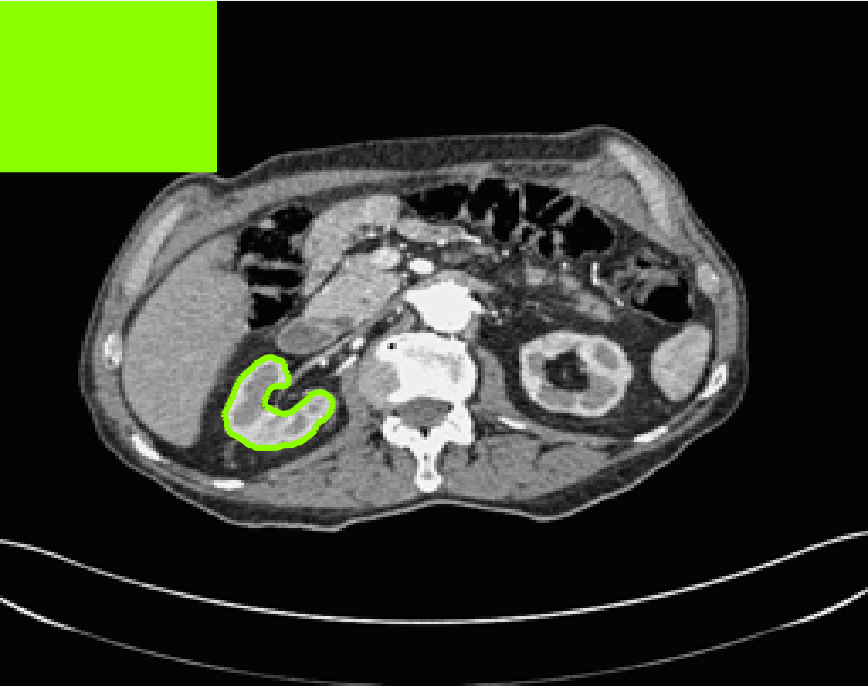

Test Images. We will perform initial tests on the images shown in Figs. 5–7. We have provided the ground truth and initialisation used for each image. Test Images 1–3 are synthetic, Test Image 4 is an MRI scan of a knee, Test Images 5–6 are abdominal CT scans, and Test Images 7–9 are lung CT scans. They have been selected to present challenges relevant to the discussion in §2. We focus on medical images as this is the application of most interest to our work. In the following we will discuss the results in terms of synthetic images (1–3) and real images (4–9). We also test the proposed approach on a larger data set of 30 CT images (a sample of which is presented in Fig. 18), comparing against existing selective methods detailed in §3.

In order to further establish the robustness of our method, we now introduce the results of testing our approach against competing interactive segmentation methods on a larger data set. The results are presented in Fig. 17, showing a boxplot of accuracy in terms of TC on a set of 30 CT images (excluding outliers). The target structure we consider is the spleen, as this consists of a relatively homogeneous foreground, appropriate for the approach considered. The data has been manually contoured providing ground truth data for the image set. We compare CAC Nguyen:12 and SRW SRW against our method with five variations of user input for each image. It is worth emphasising here that the input used in the tests is identical for each approach and was not refined in any way. It was designed to mimic what a user, unfamiliar with each approach, might select intuitively. A representative example for three images is shown in Fig. 18. This shows foreground (red) and background (blue) user input regions. For our method, we define the red region as as discussed in §1 and enforce hard constraints on the blue region. We refer to the results of the proposed approach using this input as Ours (i). We also include results of randomising the user input in an identical way to §7.3. For each image we generate 1000 simulated user input choices, which we present as Ours (ii). It is important to note that the difference between Ours (i) and (ii) is only the definition of . The method and parameters are fixed between each.

The performance of CAC Nguyen:12 is very good, as shown in Fig. 17. We have included an additional figure to highlight the difference between CAC and Ours (i) and (ii) more precisely. This is shown in Fig. 19 (this is the same as Fig. 17 with TC restricted to [0.8,1]). Here we can see that the proposed approach has a slightly better median (0.96 compared to 0.94) and is generally more consistent than CAC. This is particularly evident when considering the worst TC results of CAC () against ours ().

In Fig. 17 it can be seen that our method exceeds the performance of SRW by a large margin (0.66 compared to 0.95). One possible reason for this is that the input used, as displayed in Fig. 18, is restricted to be as intuitive as possible. SRW is capable of achieving improved results with more elaborate foreground/background input. However, it is generally reliant on a trial and error approach which is not ideal in practice. This highlights an important advantage of our method. It is able to achieve a high standard of results with simple user input. This is reinforced by considering Ours (ii), where the results of 30000 random variations of the user input does not cause a drop off in accuracy compared to the 150 manual user input selections. Again, this can be seen more clearly in Fig. 19. In fact, the results for the proposed approach with the random input are slightly better than with the manual input. This underlines the robustness to user input in the model, which is a vital aspect of selective segmentation.